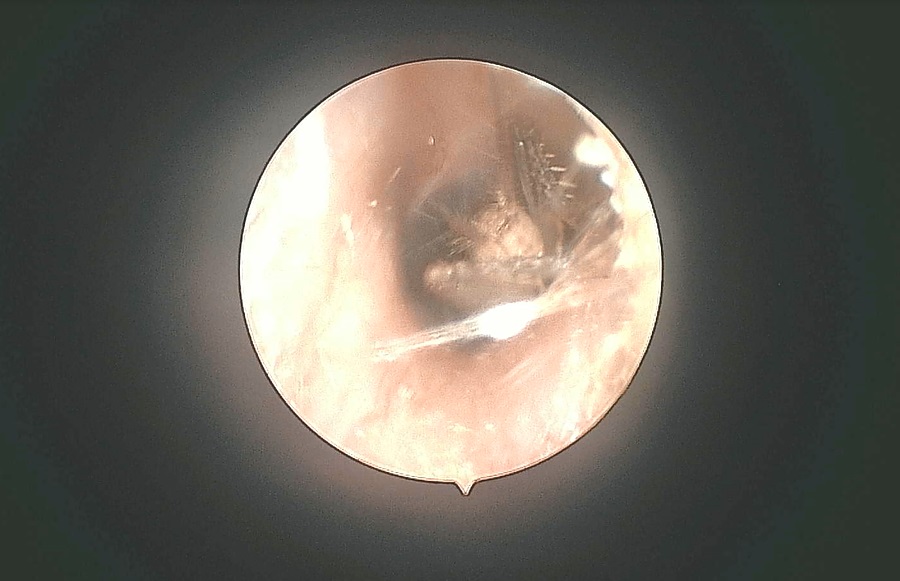

五官科主任许金中了解原因后,立即为其检查,内窥镜下,惊人一幕发生了:可以清晰的看到有一只蛐蛐,在顾先生的耳道里面蠕动。因为蛐蛐是头朝里面,钻进了狭窄的耳道,依靠外部刺激,根本不会“调头”出来,只能一直往里钻。想来这就是折磨顾先生耳朵的“罪魁祸首”。考虑到昆虫是活体时进入耳道内的,有倒钩的腿部或者口器可能已经对耳道造成了损伤。许主任决定尝试取异物,防止虫子进入耳道深处。

在内窥镜直视下,医生通过细致操作,顺利取出了一只蛐蛐,并清洗外耳道。顾先生看着取出的蛐蛐内心还是一阵悸动,想不通它是怎么钻进去的?